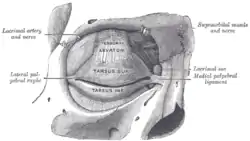

Sagittal section through the upper eyelid The tarsi and their ligaments. Right eye; front view

The tarsi and their ligaments. Right eye; front view The lacrimal apparatus. Right side